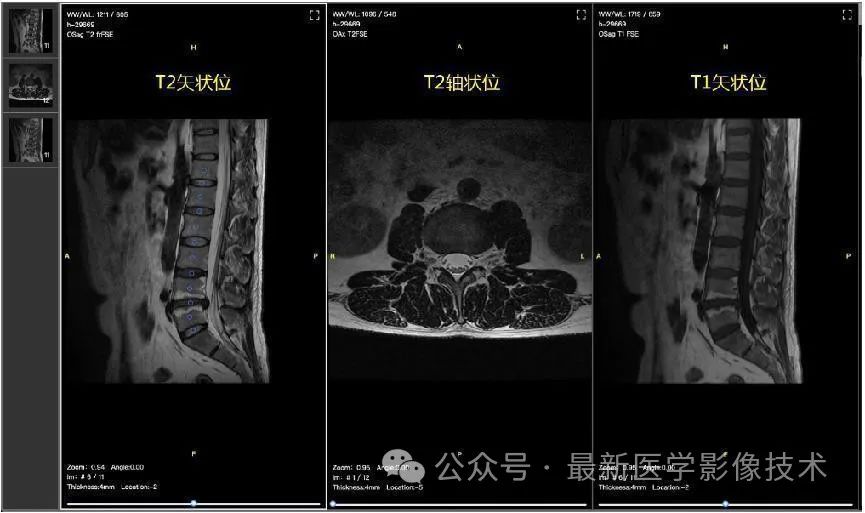

MRI数据比赛中将提供脊柱的核磁影像包括T1和T2 矢状面影像,以及T2 轴状位影像(FSE/TSE),如下图所示。初赛阶段将提供150份可下载的标注训练数据,以及50份可供下载的测试数据。复赛阶段将提供250份标注的训练数据,和100份测试数据,复赛阶段的数据不可下载。

数据标注:椎体和椎间盘的代表点会在T2矢状位的中间帧中标注出来,标注将从胸12(T12)腰1(L1)间的椎间盘开始到腰5(L5)骶1(S1)间的椎间盘结束,其中椎体的段位和椎间盘的段位将分别给出,如L1,L2,等。椎体将分成2类:正常和退行性病变,椎间盘分成5类:正常,膨出,突出,脱出,椎体内疝出。标注样例如下图。